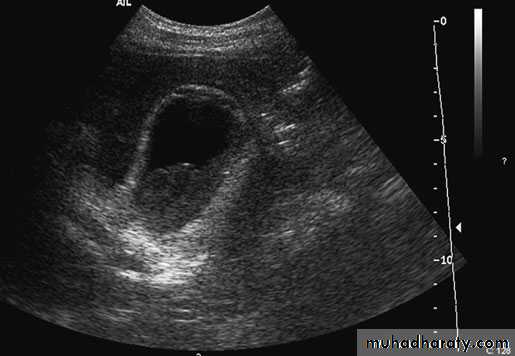

49Cholecystitis. Ultrasound demonstrates pericholecysticfluid (thin arrow), gall bladder wall (thick arrow) and biliary sludge